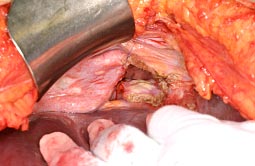

• S状結腸・直腸合併子宮・両側付属器切除術. 直腸背側を切離し、全体を授動.